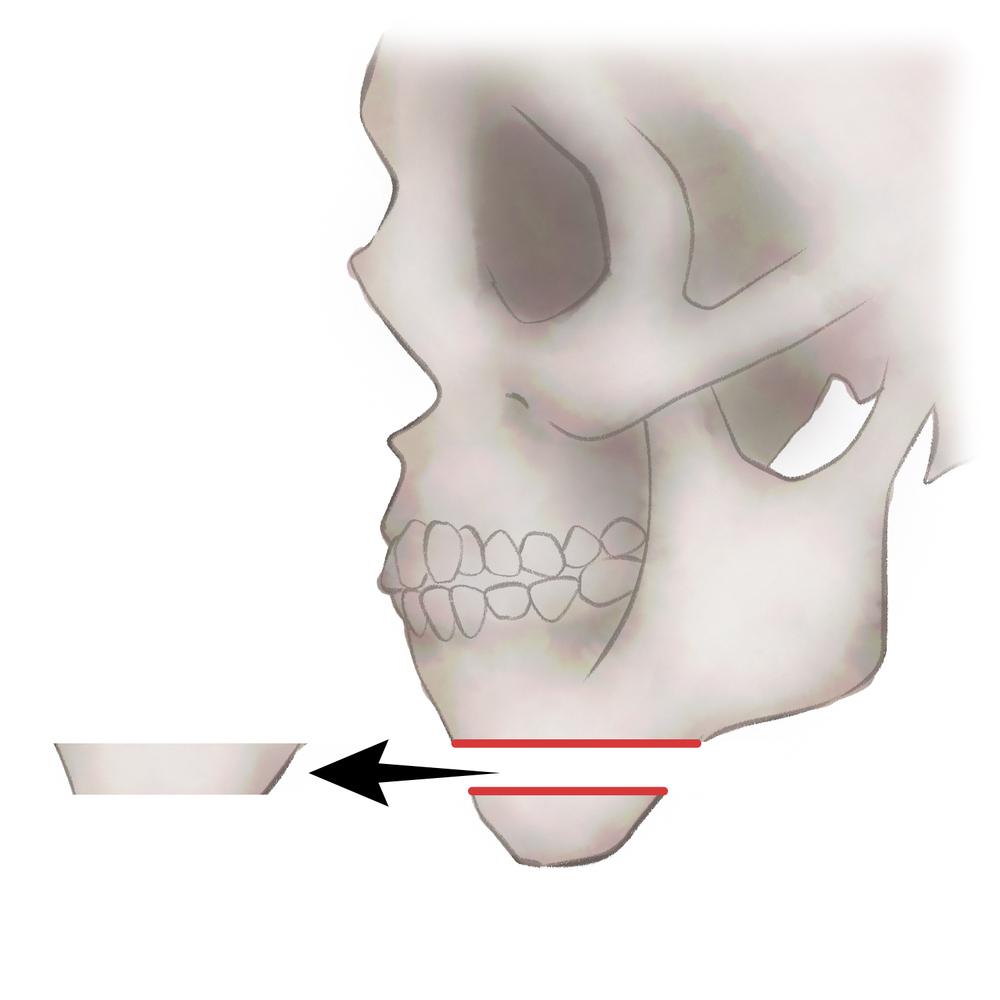

オトガイ骨切り(中抜き)

1.切開線をデザインします

2.骨を切除します

3.骨を移動させ段差を削ります

4.プレートで固定します